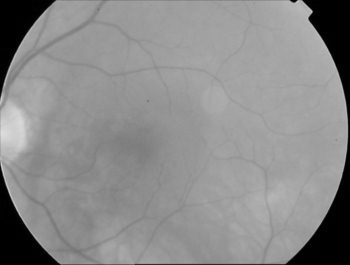

那一副醫學圖像做測試,效果確實不錯:

原圖 尺度數量為5,最大尺度為16的結果

同樣參數原始作者版本的結果,明顯沒有maltab的清晰

這個算法我測試確實對血管圖像的提取效果比較顯著,在貼幾個圖片。